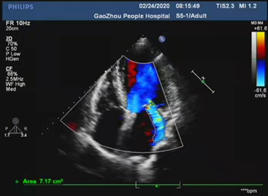

心脏彩超

主动脉瓣舒张期见中-大量红色返流,返流面积10.32cm2;

左室射血分数EF值:46%;

左室舒张末期内径(LVD):50 mm;

升主动脉增宽;

左房增大并左室增大,左室壁运动异常;

主动脉瓣评估:主动脉瓣重度关闭不全。